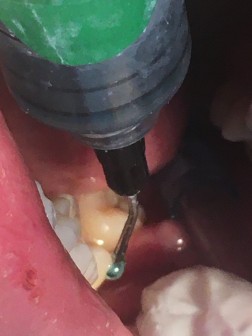

Caries avanzada, muy

cerca del tejido pulpar.

Evitando una endodoncia

con el uso de CARIESEND

El gel CARIESEND se aplica una gota y deja

actuar por dos minutos

Se aplica CARIESEND y repite el proceso hasta

lograr una cavidad limpia